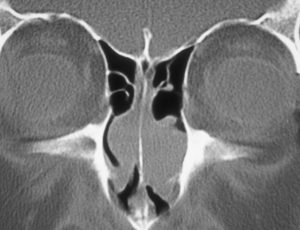

щадящая нижняя конхотомия

По объему вмешательства:

- Щадящая передняя конхотомия (удаление переднего конца раковины).

- Щадящая задняя конхотомия.

- Двусторонняя нижняя конхотомия.

- Подслизистая конхотомия.

- Высокая резекция средней носовой раковины.

- Конхэктомия – удаление всей носовой раковины вместе с костью.